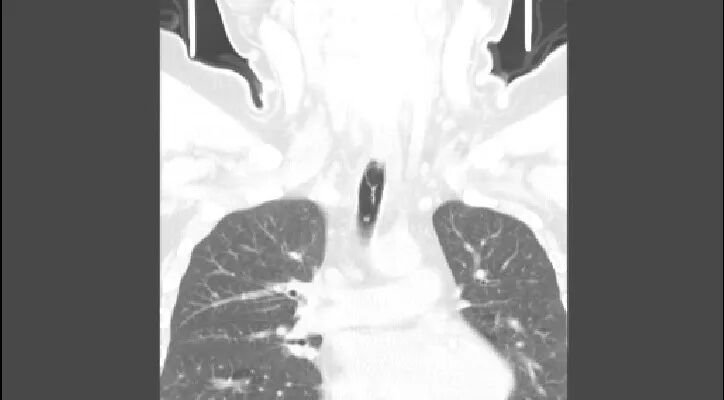

惠州三院呼吸與危重癥醫(yī)學(xué)科吳海桂主治醫(yī)師說:“這位患者是1月13日夜間與朋友一起聚餐,喝了一罐易拉罐啤酒,拉開拉環(huán)的時候沒有處理好,連同拉環(huán)一起吞到了喉部,隨后出現(xiàn)劇烈咳嗽、咳少許血痰,伴氣促,來到我院急診科完善食道CT后診斷為氣道內(nèi)異物?!?/span>

1月14日8:00,呼吸與危重癥醫(yī)學(xué)科林偉明副主任醫(yī)師為患者實施操作。支氣管鏡下,患者氣管上段有易拉罐拉環(huán)異物嵌頓,拉環(huán)頭端朝上,圓環(huán)朝下,異物取出難度大,巧妙調(diào)整異物鉗位置,通過圈套器、活檢鉗、冷凍探針等多種介入診療技術(shù)和手段,最終將異物順利取出,術(shù)中出血較少,手術(shù)達(dá)到預(yù)期目標(biāo)。整個過程歷時30分鐘,介入醫(yī)師精細(xì)嫻熟的操作過程,展示了內(nèi)鏡診療醫(yī)師的技藝和專業(yè)素養(yǎng)。